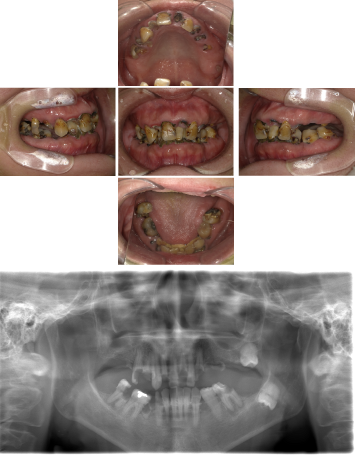

50代 インプラント治療(右上3左上3のみGBR)

| 年代・性別 | 50代・男性 |

| 主訴 | 入れ歯が合わず毎日ヨーグルトしか食べることができないので、しっかり咬めるインプラントにしたい。 |

| 部位 | 右下⑦⑥5④ 上顎③2①①2③ 左下67 |

| 治療期間 | 約9ヶ月 |

| 費用 | ¥4,273,500(税込) |

| 副作用・リスク |

|